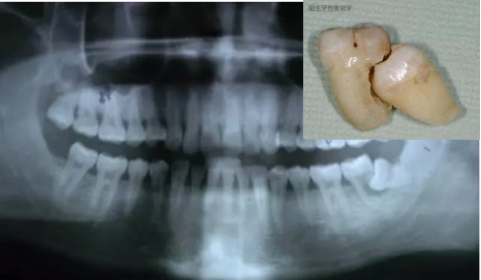

阻生牙(impacted teeth)是指部分萌出或完全不能萌出,且以后也不会自行萌出的牙。好发部位为下颌第三磨牙、上颌第三磨牙及上颌尖牙,其中阻生第三磨牙也叫做阻生智齿。

2、龋齿:阻生的智齿与第二磨牙之间容易积存食物残渣,而且不易清洁,很容易形成智齿和第二磨牙的龋齿而发生疼痛。